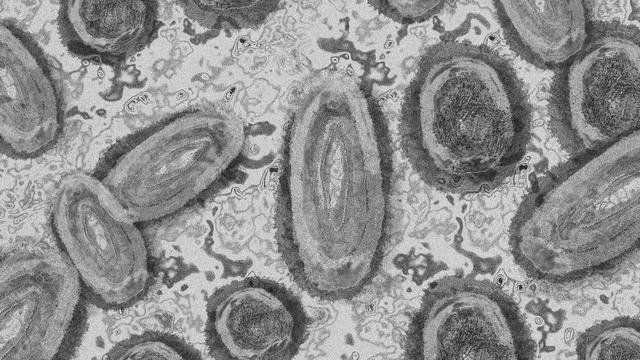

Liputan6.com, Jakarta - Penyakit cacar monyet (monkeypox) menjadi salah satu yang menimbulkan kekhawatiran masyarakat di tengah pandemi COVID-19 yang masih terus menghantui. Berbagai informasi mengenai cacar monyet telah menyebar luas dengan sangat cepat. Seperti gejala, tanda-tanda fisik, cara penularan, hingga metode pencegahan tersebarnya cacar monyet.

Menurut hasil studi terbaru yang diterbitkan oleh Annals of Internals Medicine, para peneliti mejelaskan bahwa beberapa orang yang dites untuk mendeteksi cacar monyet (monkeypox) dinyatakan tidak menunjukkan adanya gejala.